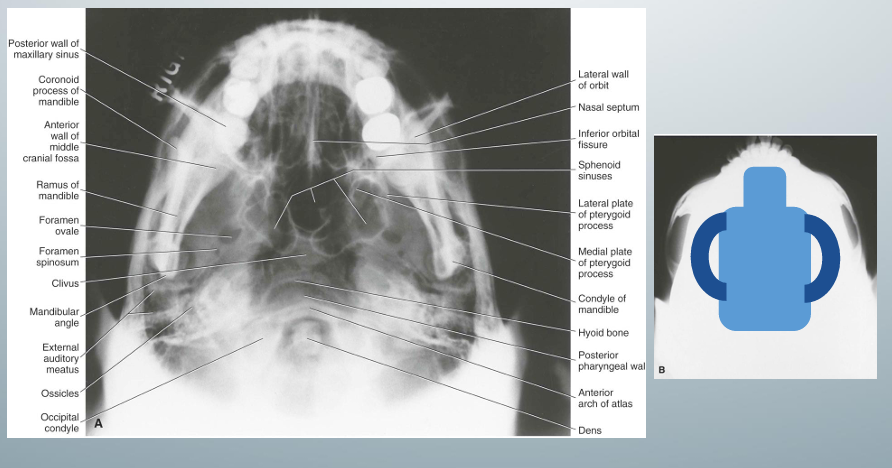

submentovertex view

-”jug handle view” because zygomatic arches stand out like the handles of a jug handle

-used for zygomatic arch fracture evaluation

-underexposure recommended to visualize zygomatic arches well

submentovertex view- uses, image receptor placement, pt position, central x-ray beam position, notes

how to take submentovertex view

-image receptor placed parallel to pt’s transverse plane and perpendicular to the midsagittal and coronal planes

-pt needs to extend neck as far back as possible such that the canthomeatal line could form a 10 degree angle with image receptor

-central x-ray beam position directed below the mandible toward the vertex of the skull and centered to 2cm anterior to a line connecting the right and left mandibular condyles